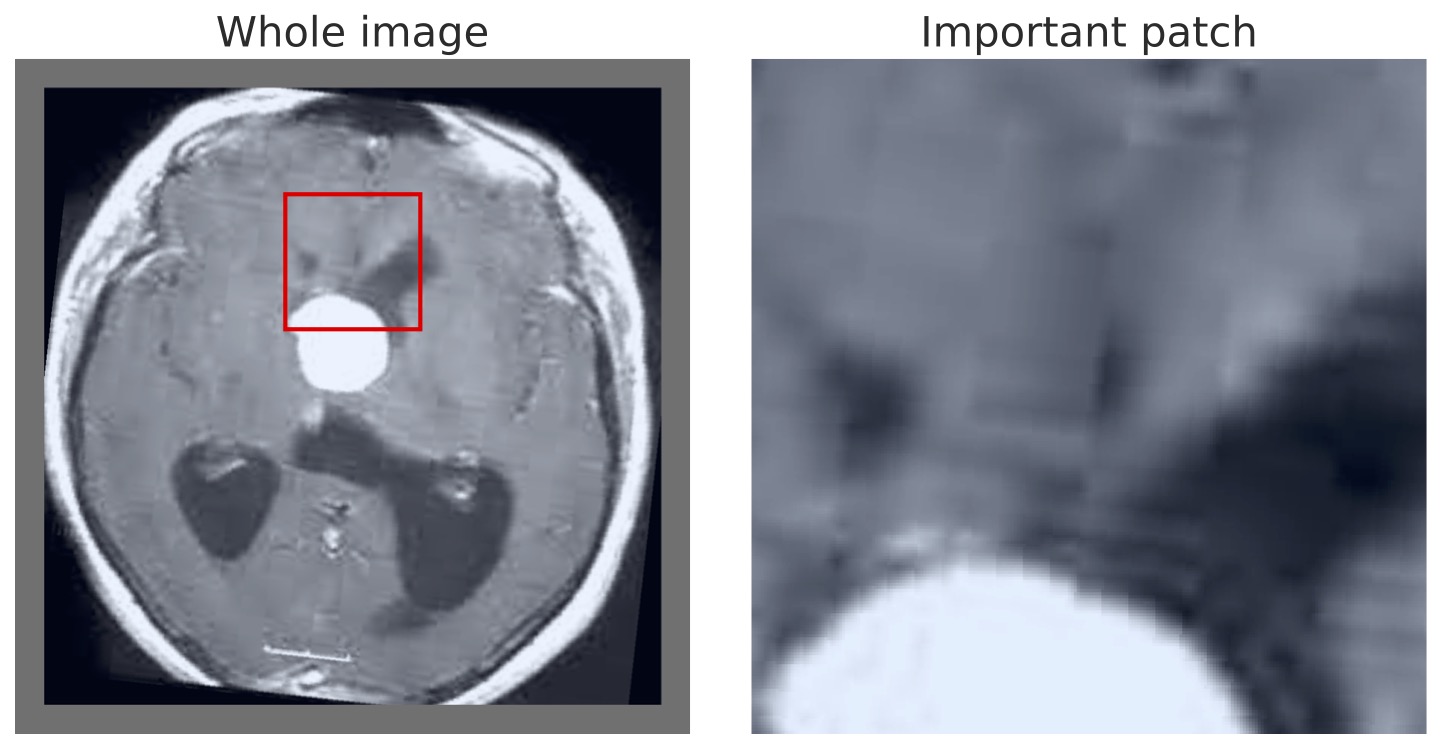

Finally, we can also visualize the results of our MIL model in the same manner as prior approaches, highlighting either the most positive, or all positive, regions to allow interpretable inspection and verification. This is demonstrated in Figure 6 using the BTMD dataset, in which tumors are recognizable to non-medical experts. The appendix has additional random samples from the other dataset.

In Figure 9 we show multiple BTMD images randomly selected and the maximal positive detection region from each image. In each case it is clear that the model successfully focuses on the malignant portions.

VSA-MIL further succeeds in detecting more than just the singular region of malignancy. This is confirmed by visualizing all overlapping sub-regions that are detected as positive malignancy, demonstrated in Figure 11. We make note that in some cases adjusting the size of the patch may yield more intuitive results depending on the size of what needs to be detected, but did not alter this to be aligned with prior articles and the patch size previous used.